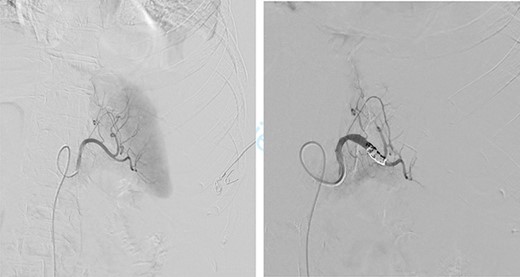

On the sixth post-operative day, the patient suddenly felt weak. She presents with pallor, hypotension and tachycardia. We noticed some blood in the left drain. We immediately started a fluid resuscitation and performed an urgent CT which showed a fresh 6-cm wide splenic sub capsular hematoma associated with a major hemoperitoneum (Fig. 2).